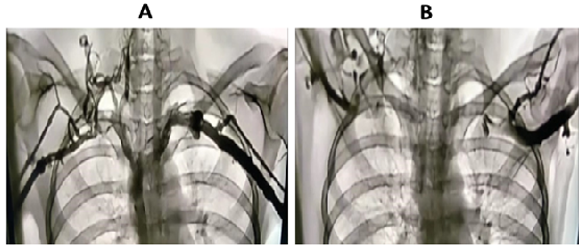

Recently, examination of the medial aspect of the resected first ribs in patients with Paget–Schroetter syndrome has demonstrated the presence of a congenitally malformed bony tubercle that forms a tighter and wider joint at the junction of the first rib and the sternum [4-6]. (Figure. 2)

Figure 2: Preoperative MRA with maneuvers in a patient with Paget Schroetter Syndrome. The Arrows point to the extrinsic compression of the subclavian vein at its junction with the innominate vein by a bony protuberance on the underside of the vein.

It has been observed that the wider and less mobile cost-sternal joint “locks” the medial aspect of the first rib into place and results in extrinsic compression of the boney tubercle onto the subclavian vein at its junction with the innominate vein. It can be surmised that without the benefit of the sophisticated modern imaging, and relying only on intraoperative observations, it is likely that historically surgeons have erroneously referred to this tubercle as the hypertrophied costoclavicular ligament and the hypertrophied scaleneus anticus tubercle. This abnormal tubercle on the medial aspect of the first rib can be seen on 3-D reconstruction of computerized axial tomograms in patients with PSS. (Figure. 3) In addition, the extrinsic compression of the subclavian vein by the tubercle at the medial aspect of the first rib can be demonstrated on dynamic magnetic resonance angiography (MRA) with maneuvers and dynamic venography. (Figures. 4a, 4b)